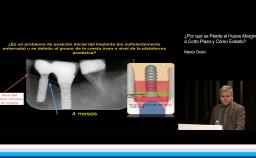

The rehabilitation of posterior mandible with dental implants represents a difficult challenge for clinicians due to the lack of supporting bone. The alveolar nerve presence and the gradual vertical and horizontal resorption of the mandibular bone crest in both partially and totally edentulous patients can be treated by several surgical options - vertical ridge augmentation, surgical displacement of the inferior alveolar nerve, or the placement of short implants (8 mm or less).

This lecture presents the different surgical techniques currently being used to vertically augment the posterior mandible: guided bone regeneration (GBR), alveolar distraction osteogenesis, and onlay bone grafting; however, few of these techniques have been tested in a randomized clinical trial (RCT), and some bone augmentation techniques are complicated by an unpredictable resorption of the grafted material.